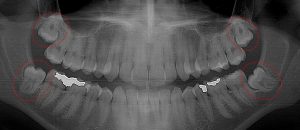

This 19 year old patient has all four 3rd molars present (circled). The roots are +90% formed. Both lower 3rd molars are impacted against the 2nd molars with no chance of further eruption and a +60% probability of decaying before age 30. The patient presented with pain and infection around both lower 3rd molars, requiring immediate extraction

This 48 year old patient had all four 3rd molars extracted in his late 20’s. All four sites healed poorly and chronically infected bony defects remained. The upper right 2nd molar was extracted two years ago as a result of this chronic infection. The upper left 2nd molar must now be extracted because of a chronic periodontal infection moving around that tooth. Both lower molars are chronically infected and have a poor prognosis.